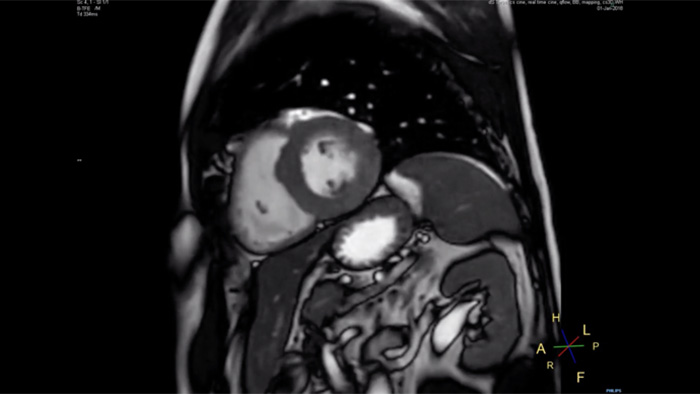

Up to 40% reduction in breathholds, with virtually equal image quality1

Philips Compressed SENSE reduces the time spent in the MRI scanner for the patient. Furthermore, Compressed SENSE enables the reduction of breath hold times which has the potential to improve compliance with an MRI scan.

4.8 sec breath hold time

Since short breath hold times make it easier for our patients to comply, the failure of breath holding largely disappeared.

At our facility, we found in Cardiac MR fewer breath holds are now needed, or breath hold times are shortened."

Dr. Takashi Koyama, MD, PhD, Diagnostic Radiologist and Director of the Department of Radiology Center and Diagnostic Radiology, Kurashiki Central Hospital, Japan

A 15- or 16-second breath-hold is tough for many cardiac patients. With Compressed SENSE we actually have protocols now that can get that below 10 seconds. It’s a lot easier to get through for a patient, and patients are a lot more satisfied with the experience.”

Trevor Andrews, Ph.D., MR Physicist, University of Vermont Medical Center, USA